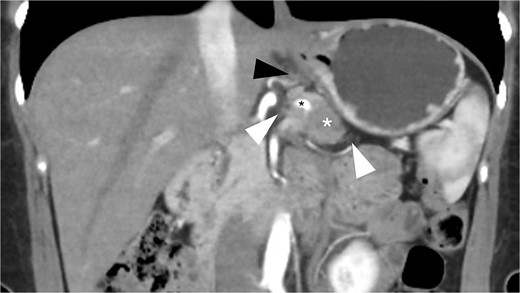

A 49-year-old female patient underwent RAMPS for resectable pancreatic duct adenocarcinoma (PDAC) located in the body of the pancreas. Her preoperative CA19-9 levels were 20.51 IU/ml. Computed tomography (CT) revealed a 25 mm infiltrating mass at the level of the dorsal aspect of the body of the pancreas, associated with mild sinistral portal hypertension and invasion of the left adrenal gland, retroperitoneal fat, and splenic vessels (Fig. 1). Posterior RAMPS was performed to ensure adequate margins. During surgery, we confirmed that the mass had infiltrated the splenic vessels and LGV, and ingurgitation was observed along with other varicose veins in the stomach.

Preoperative CT scan (coronal view, portal phase) shows a 25 mm spiculated mass with hypoattenuation observed after the administration of IV contrast (white asterisk). The lesion encases the splenic artery (black asterisk), extends to the retroperitoneal fat (white arrowhead), and shows mesogastric distortion (black arrowhead).